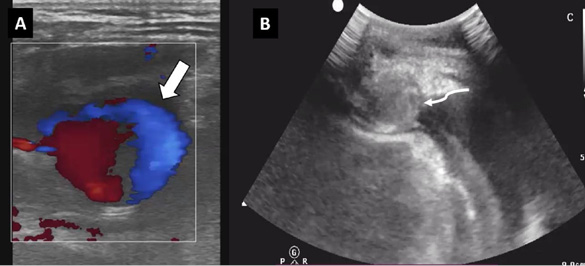

A follow-up ultrasound one week later showed the outpouching, which initially had displayed the “ying-yang” phenomenon at presentation (Figure 3A), now showing echogenic contents completing filling it (Figure 3B), thus indicating complete thrombosis of the pseudoaneurysm. Follow-up echocardiograms at 1 week and 2 weeks post-procedure were normal without any hemopericardium.